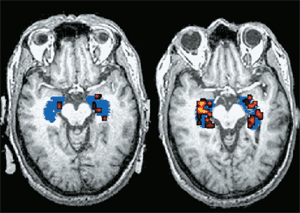

4. Одумирање коре великог мозга

Мозак, као и многи други органи, пати од вишка шећера. Често, с временом, део мождане коре умире у дијабетесу и развијају се неповратни ментални поремећаји: особа престаје препознавати чланове своје породице, не може обављати елементарне активности и бринути се о себи.